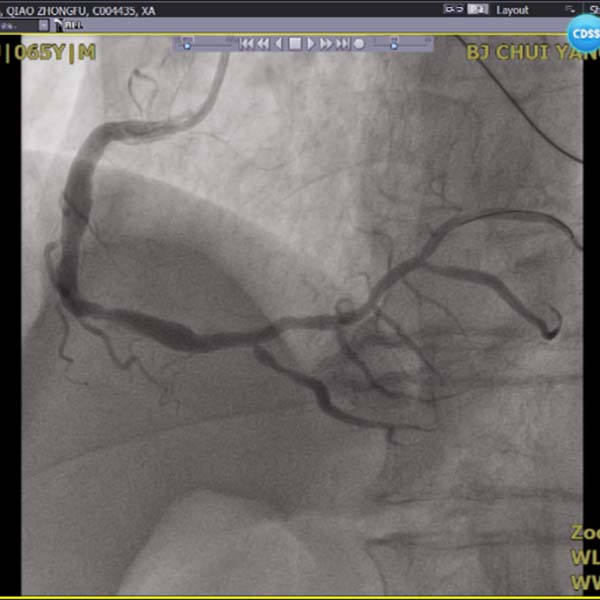

2022年1月2日,一名急性心梗患者经急诊介入治疗将右冠脉进行血栓抽吸后置入一枚支架,成功开通罪犯血管后,收入CCU病房。